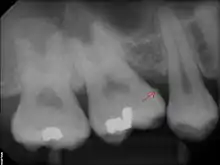

The processes of calculus formation from dental plaque are not well understood. Supragingival calculus formation is most abundant on the buccal (cheek) surfaces of the maxillary (upper jaw) molars and on the lingual (tongue) surfaces of the mandibular (lower jaw) incisors.[15] These areas experience high salivary flow because of their proximity to the parotid and sublingual salivary glands. Subgingival calculus forms below the gumline and is typically darkened in color by the presence of black-pigmented bacteria,[15] whose cells are coated in a layer of iron obtained from heme during gingival bleeding.[16] Dental calculus typically forms in incremental layers[17] that are easily visible using both electron microscopy and light microscopy.[9] These layers form during periodic calcification events of the dental plaque,[15] but the timing and triggers of these events are poorly understood. The formation of calculus varies widely among individuals and at different locations within the mouth. Many variables have been identified that influence the formation of dental calculus, including age, gender, ethnic background, diet, location in the oral cavity, oral hygiene, bacterial plaque composition, host genetics, access to professional dental care, physical disabilities, systemic diseases, tobacco use, and drugs and medications.[15]

Sub-gingival calculus is composed almost entirely of two components: fossilized anaerobic bacteria whose biological composition has been replaced by calcium phosphate salts, and calcium phosphate salts that have joined the fossilized bacteria in calculus formations.[37][38] The initial attachment mechanism and the development of mature calculus formations are based on electrical charge.[39] Unlike calcium phosphate, the primary component of teeth, calcium phosphate salts exist as electrically unstable ions. The following minerals are detectable in calculus by X-ray diffraction: brushite (CaHPO4 · 2 H2O), octacalcium phosphate (Ca8H2(PO4)6 · 5 H2O), magnesium-containing whitlockite (Ca9(Mg,Fe)(PO4)6(PO3OH)), and carbonate-containing hydroxyapatite (approximately Ca5(PO4)3OH but containing some carbonate).[40]